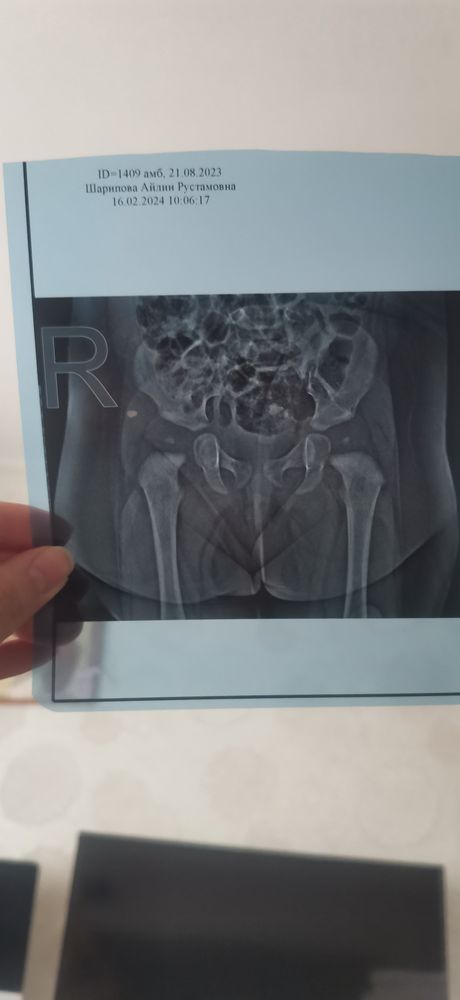

Альбина в Развитие от рождения до года 2 года Рентген тбс Обсуждение диагнозов Кто разбирается в рентгене тазобедренных суставов ? Посмотрите еще 20 записей на эту тему Отменить Ответить Елена К ортопеду на консультацию. Так то ацетабулярные углы в норме, но справа у сустава линия шентона нарушена. Может гимнастику какую пропишет 16.02.2024 Ответить Альбина Елена, сходили, сказала все хорошо у нас. Назначила массаж +лфк 16.02.2024 Ответить Алина А Так рентген суставов не смотрят. Нужно смотреть вблизи, изменять углы и т д. Там только врач сможет 16.02.2024 Ответить Альбина Алина А, спасибо поняла 16.02.2024 Ответить Коклюш страх и ужас Срыгивает носом Чаты Беременных Выберите чат: Январята-2026 Февралята-2026 Мартята-2026 Апрелята-2026 Майчата-2026 Июнята-2026 Июлята-2026 Августята-2026